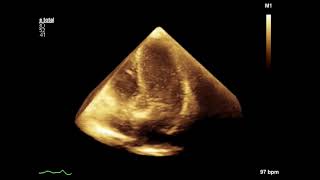

60 Seconds Of Echo Teaching Question What Is The...

60 Seconds Of Echo Teaching Answer What Is The...

60 Seconds Of Echo Teaching Question How Would...

60 Seconds Of Echo Teaching Answer How Would You...

60 Seconds Of Echo Teaching Question What Should...

60 Seconds Of Echo Teaching Answer The Heart Of A...

60 Seconds Of Echo Teaching Question Calcium,...

60 Seconds Of Echo Teaching Answer How Do You...

60 Seconds Of Echo Teaching Answer Where Is The...

60 Seconds Of Echo Teaching Answer Is Ef A Good...

60 Seconds Of Echo Teaching Answer Aortic...

60 Seconds Of Echo Teaching Answer Identify 10...

60 Seconds Of Echo Teaching Answer Echo After...

60 Seconds Of Echo Teaching - Hypertension

60 Seconds Of Echo Teaching Answer A Simple...

60 Seconds Of Echo Teaching Question A Strange...

60 Seconds Of Echo Teaching Answer What Should...

60 Seconds Of Echo Teaching Answer Which...

60 Seconds Echo Tavi

60 Seconds Of Echo Teaching Question Congenital...

60 Seconds Of Echo Teaching Answer Echo In Liver...

60 Seconds Of Echo Teaching Answer How Will Lvf...